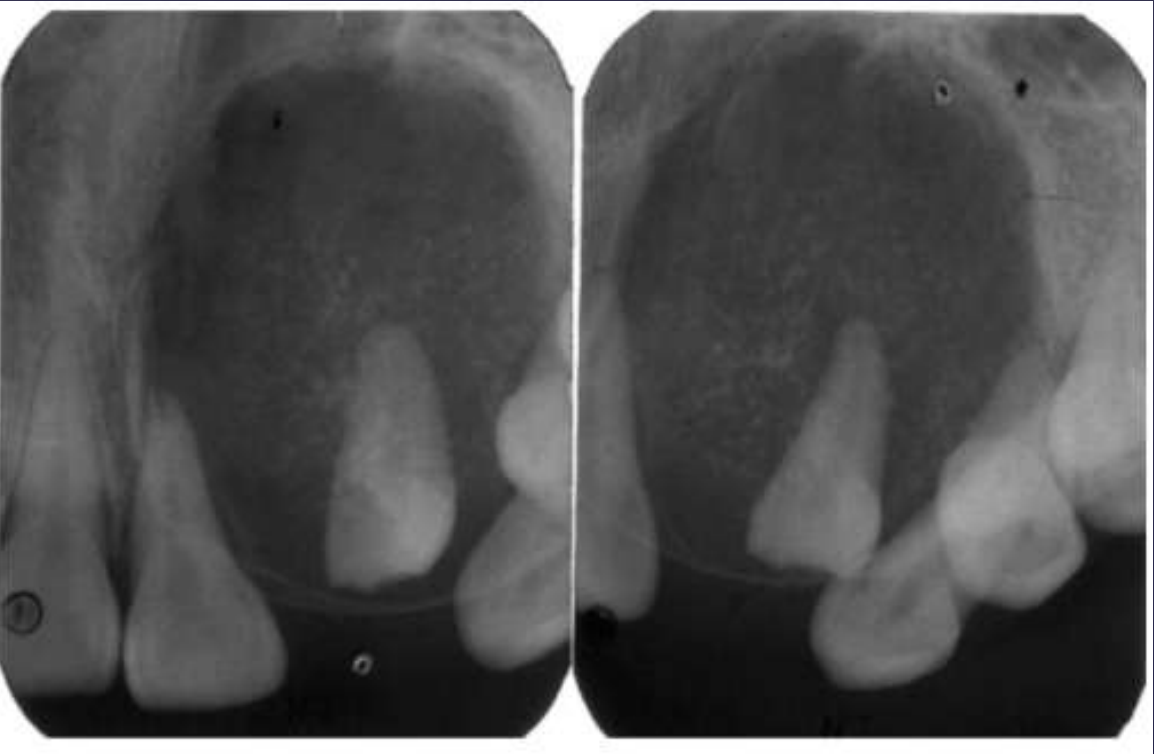

COMPOUND odontomas

• Well defined, corticated

• Radiolucent band/soft tissue capsule inside the cortical border

• Internal content is largely radiopaque- made of multiple tooth like structures called denticles

• Maybe be associated with unerupted tootH

COMPLEX odontomas

Well defined, corticated

Radiolucent band/soft tissue capsule inside the cortical border

Internal content is largely radiopaque- made of irregular mass of calcified tissue

Maybe be associated with unerupted tooth

Possible displacement of teeth (30, 29)

Compound –Complex Odontoma

Well defined

Mixed density, corticated

Combination of amorphous radiopaque mass and tooth like structures

Osseous expansion

Thinning of cortices

Displacement of teeth, unerupted tooth